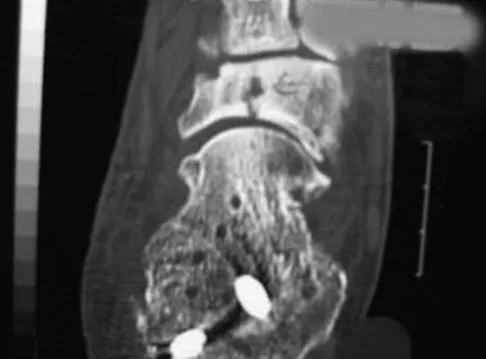

A 51-year-old male truck driver has had progressive left hip pain for more than 2 years, and he reports that the pain has become severe in the past 9 months. He is now unable to work because of the pain. Examination reveals that range of motion of the hip is limited to 95 degrees of flexion, 0 degrees of internal rotation, and 20 degrees of external rotation. The plain radiograph, MRI scan, and intraoperative gross photographs are shown in Figures 9a through 9d. Management should consist of